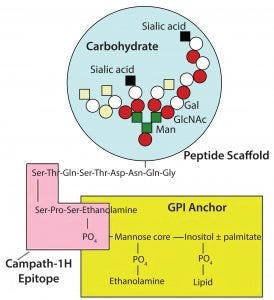

Campath antibodies recognize an epitope very close to the cell membrane (Figure 8). The proximity of that epitope to the cell membrane is one of the reasons why Campath is such a good antibody for killing cells. The antibody delivers that lytic target only to places where it is needed (close to the cell membrane). Other antibodies that are effective at killing cells almost always tend to bind closely to the cell membrane.

Figure 8: Campath antibodies recognize an epitope very close to the cell membrane